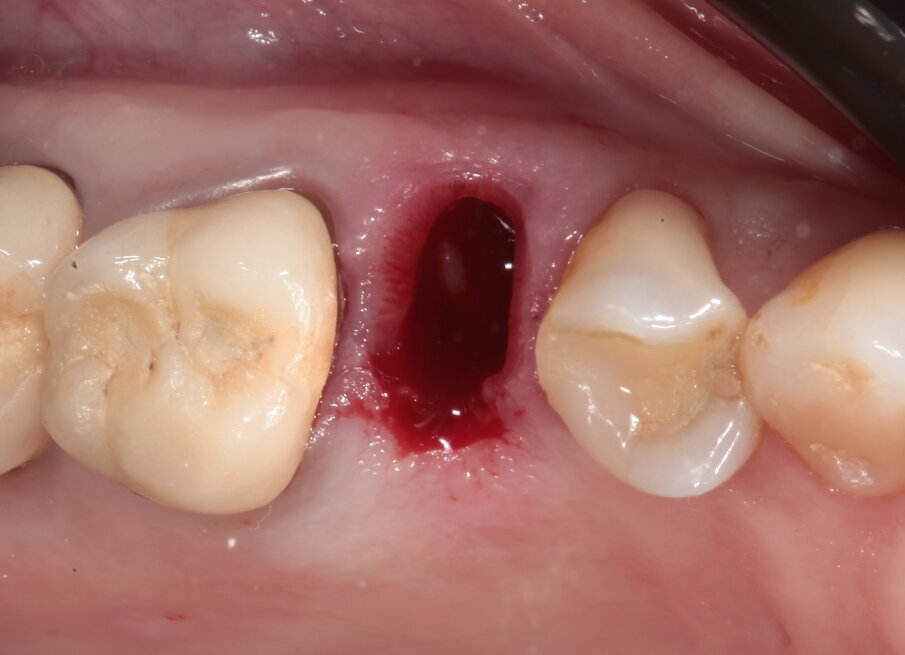

La paziente si presenta in visita lamentando mobilità e l’insorgenza di un dolore alla masticazione a carico dell’elemento 25. Clinicamente l’elemento presenta una corona in ceramica integrale realizzata anni prima (non ricorda quanti) presso altra sede, mobilità di II grado e sondaggio di 9 mm sul versante palatale.

Il piano di trattamento prevede quindi l’estrazione del 25 giudicato non mantenibile, la preservazione dell’alveolo post estrattivo, l’inserimento differito di un impianto e il suo carico una volta terminato il processo di osteointegrazione. Per quanto riguarda l’elemento 24, si programma la terapia endodontica e la successiva ricostruzione diretta. Viene effettuata un’estrazione atraumatica del 25, la rimozione del tessuto infiammatorio periapicale e il posizionamento di un sostituto osseo addizionato con acido ialuronico reticolato ad alto peso molecolare (HyaDENT BG) al fine di ottenere una più rapida stabilizzazione del coagulo ed una buona stabilità dell’innesto, determinanti per il mantenimento del volume ottimale. Questo viene poi coperto con una membrana di collagene suino imbustata al di sotto dei tessuti vestibolari e palatali (Figg. 6-10).